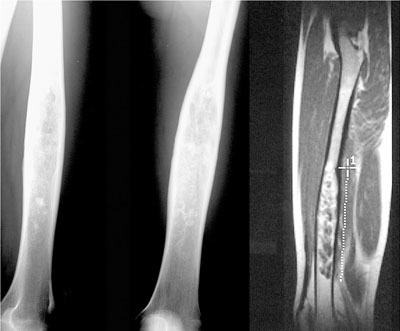

Quel diagnostic pour cette tumeur osseuse?

Chondrome de la diaphyse fémorale car matrice cartilagineuse